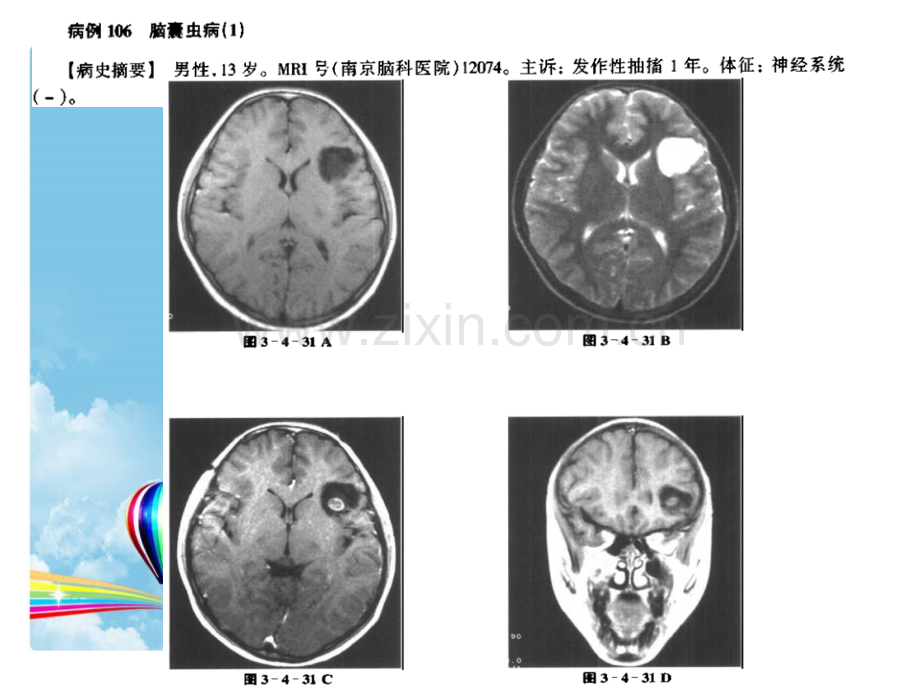

2012-8-27颅内感染的MRI诊断5脑囊虫病沈丘县中医院郑洪喜